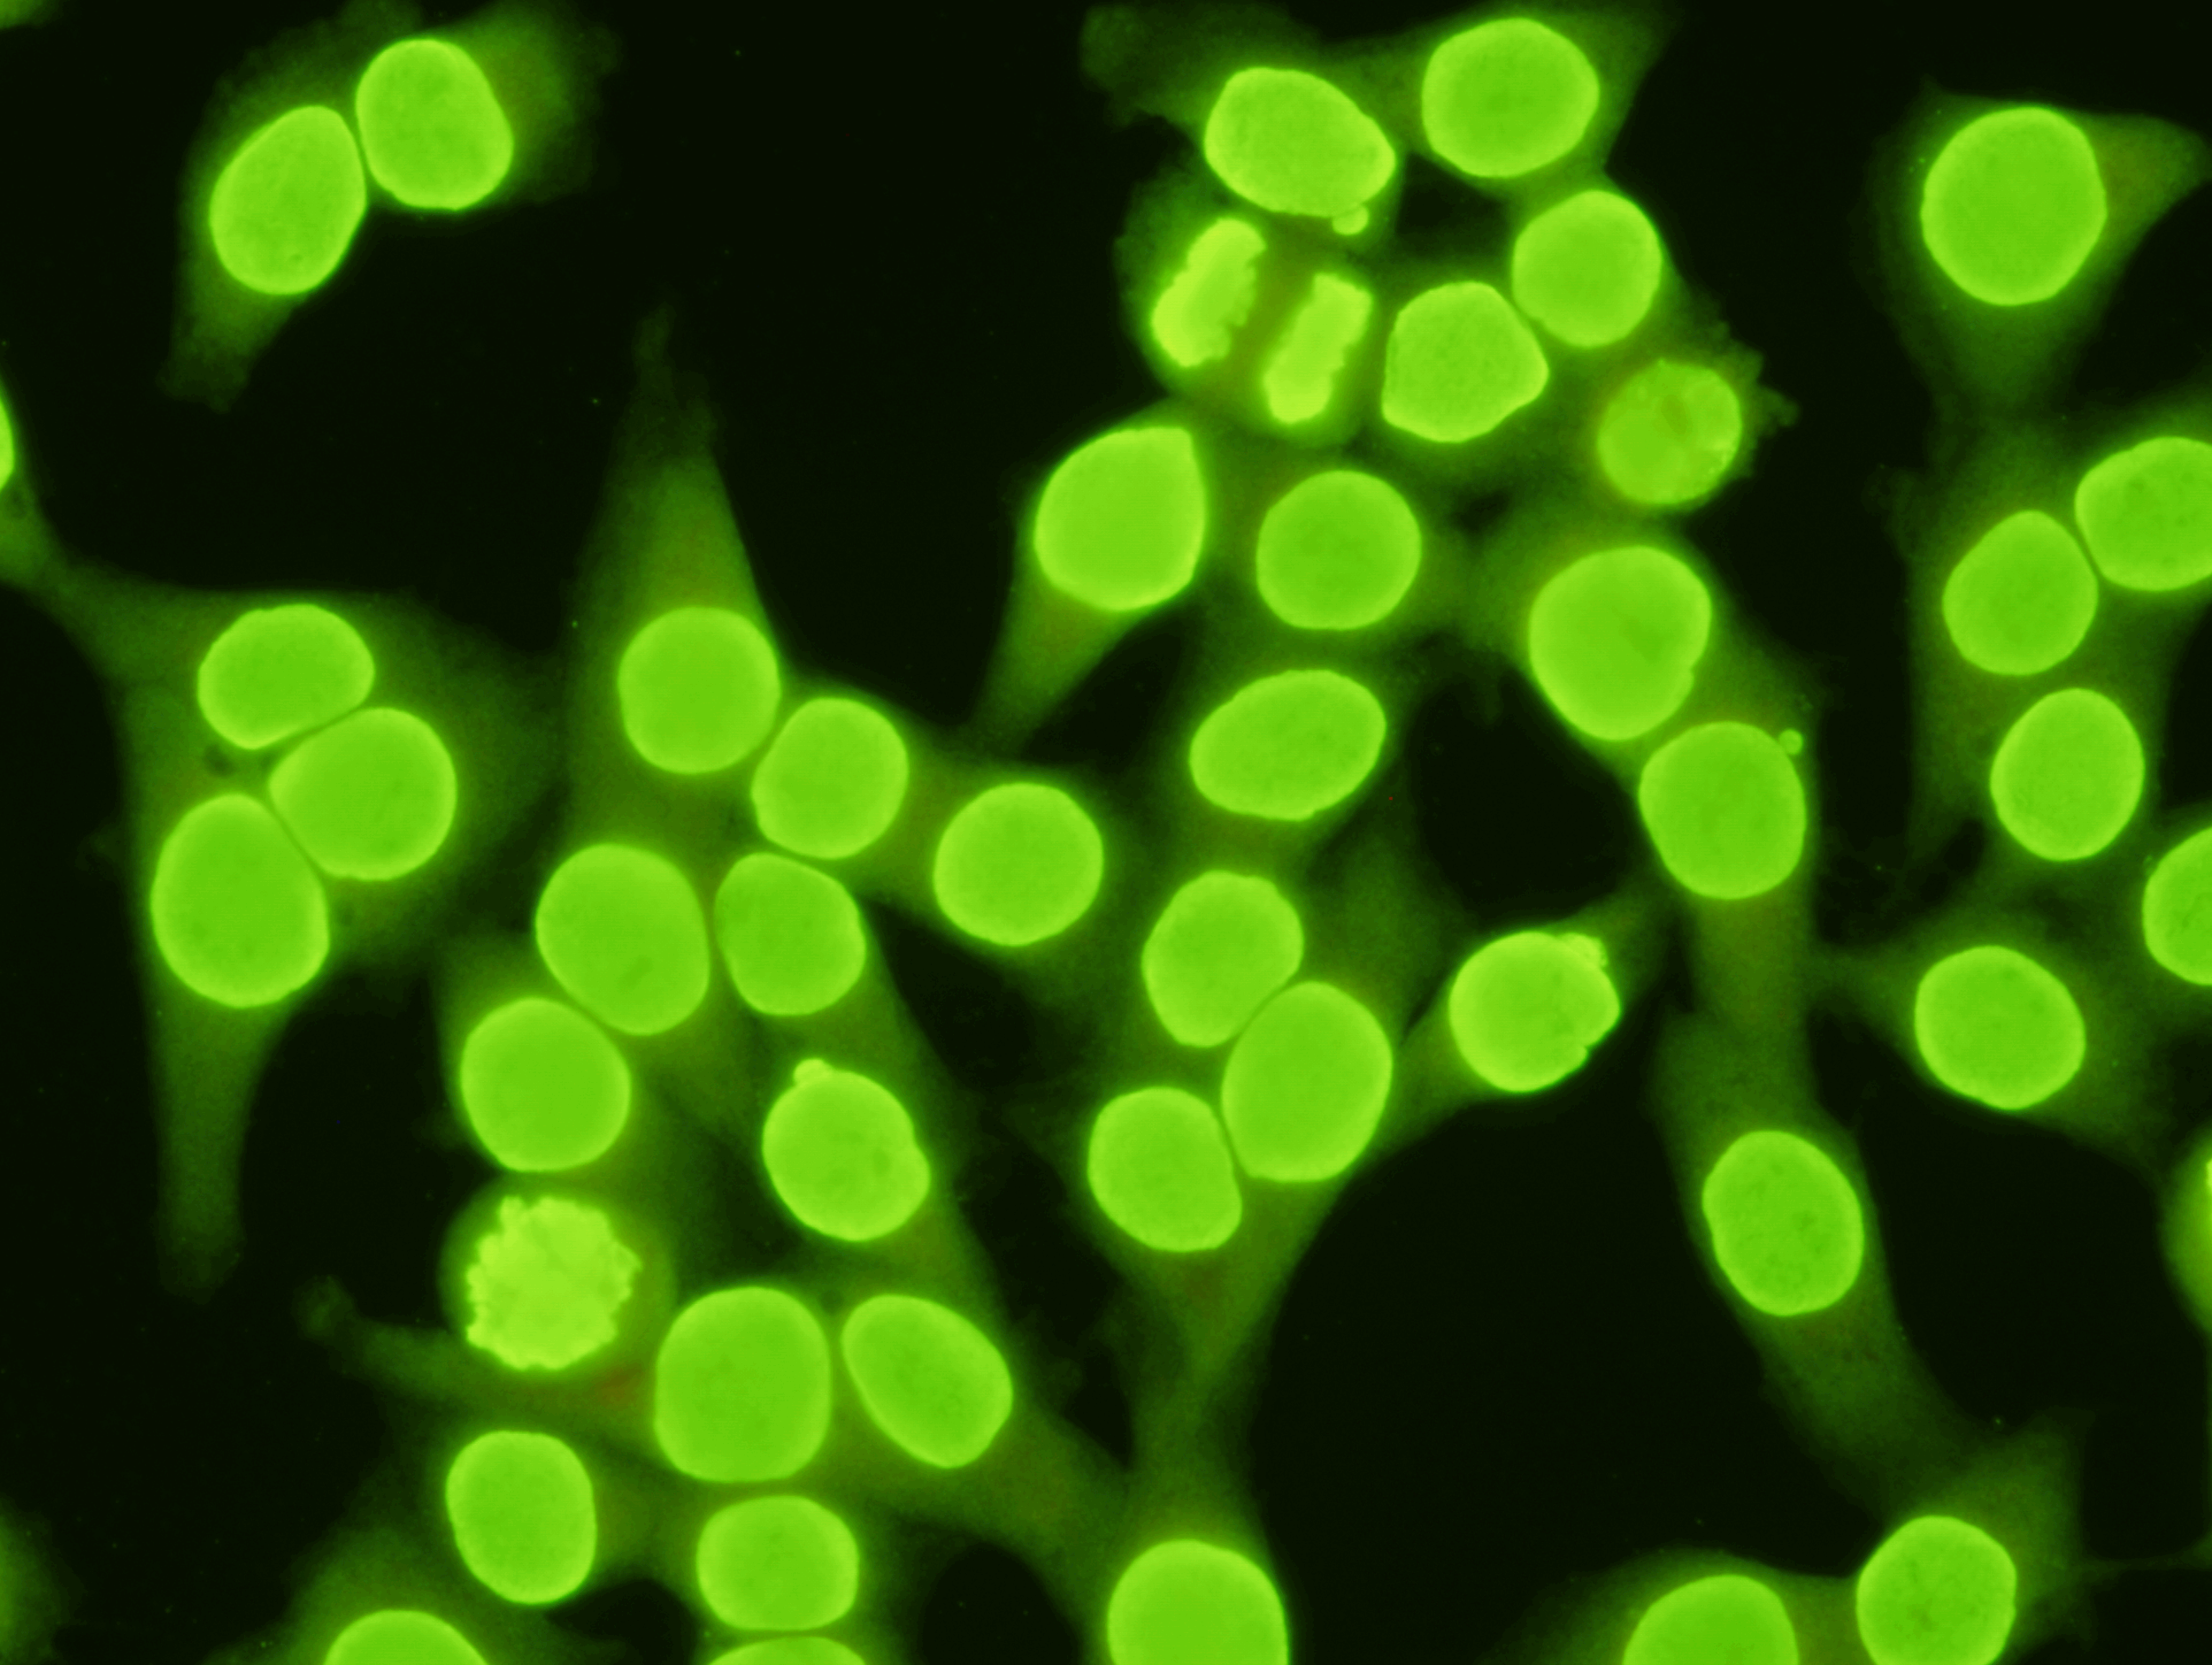

C-ANCA Test Kit  Indirect Immunofluorescence assay for the detection of Anti-Neutrophil Cytoplasmic antibodies in human serum using ethanol fixed human neutrophils as substrate.  This test is intended as an aid in the diagnosis of Wegener's gra

C-ANCA Test Kit

Indirect Immunofluorescence assay for the detection of Anti-Neutrophil Cytoplasmic antibodies in human serum using ethanol fixed human neutrophils as substrate.  This test is intended as an aid in the diagnosis of Wegener's granulomatosis, Idopathic Crescentic Glomerulonephritis, Microscope Polyarteritis and Pulmonary Renal Syndrome.

A060L  60 Test Kit